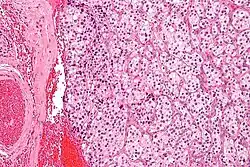

| Micrograph of a carotid body tumor (a type of paraganglioma) | |

The paragangliomas appear grossly as sharply circumscribed polypoid masses and they have a firm to rubbery consistency. They are highly vascular tumors and may have a deep red color.

On microscopic inspection, the tumor cells are readily recognized. Individual tumor cells are polygonal to oval and are arranged in distinctive cell balls, called Zellballen.[9] These cell balls are separated by fibrovascular stroma and surrounded by sustentacular cells.

By light microscopy, the differential diagnosis includes related neuroendocrine tumors, such as carcinoid tumor, neuroendocrine carcinoma, and medullary carcinoma of the thyroid.

With immunohistochemistry, the chief cells located in the cell balls are positive for chromogranin, synaptophysin, neuron specific enolase, serotonin, neurofilament and Neural cell adhesion molecule; they are S-100 protein negative. The sustentacular cells are S-100 positive and focally positive for glial fibrillary acidic protein. By histochemistry, the paraganglioma cells are argyrophilic, periodic acid Schiff negative, mucicarmine negative, and argentaffin negative.

Micrograph of a carotid body tumor

Micrograph of a carotid body tumor -